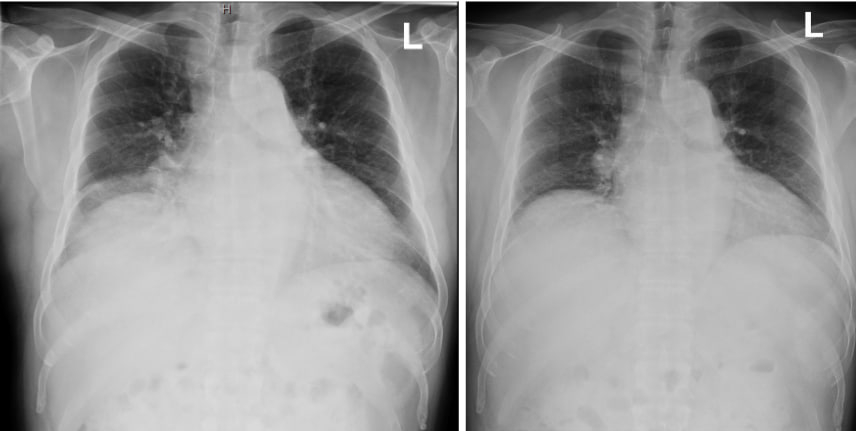

Case Description: A 58-year-old man with diabetes and poorly controlled hypertension presented with three days of hemoptysis. He denied other episodes of overt bleeding, chest pain, arthralgias, weight loss, or fever. He had a prior history of treated latent tuberculosis. He traveled to Las Vegas and noted a blow of moldy dust which he recalled as the only significant recent exposure. On arrival, BP was elevated at 206/131 mm Hg, but he was otherwise hemodynamically stable. Troponin was mildly elevated but later normalized. CBC and BMP were unremarkable. Inflammatory markers were minimally elevated (CRP: 3 mg/L, ESR: 10 mm/hr). CT chest showed diffuse bilateral ground-glass opacities. Bronchoscopy with BAL revealed friable mucosa and progressively bloody aliquots, confirming DAH. There was no evidence of malignancy or infection from BAL analysis. Extensive workup for DAH, including ANA, ANCA, cryoglobulins, anti-GBM, QuantiFERON, AFB smears and cultures, Leptospira, Legionella, Strongyloides, fungal, and bacterial cultures, was negative. TTE demonstrated normal EF and moderate LV hypertrophy; there was no valvular abnormality. With no alternate etiology, severely uncontrolled hypertension was deemed the most likely cause of DAH, supported by a few published case reports. The patient was started on nifedipine 60 mg and losartan 50 mg daily. With improved blood pressure for the remainder of his hospital stay, hemoptysis gradually resolved. At the post-hospital visit, he remained asymptomatic with good blood pressure control and complete resolution of lung opacities on imaging.

Conclusion: Severe hypertension can cause end-organ damage, affecting the heart, brain, and kidneys; however, DAH is a poorly recognized complication. Proposed mechanisms include alveolar capillary stress failure, microvascular endothelial injury, and pulmonary venous hypertension. While DAH is a rare presentation of severe hypertension with very few cases reported in the literature, our case highlights this unique complication and the importance of strict blood pressure control in its management.